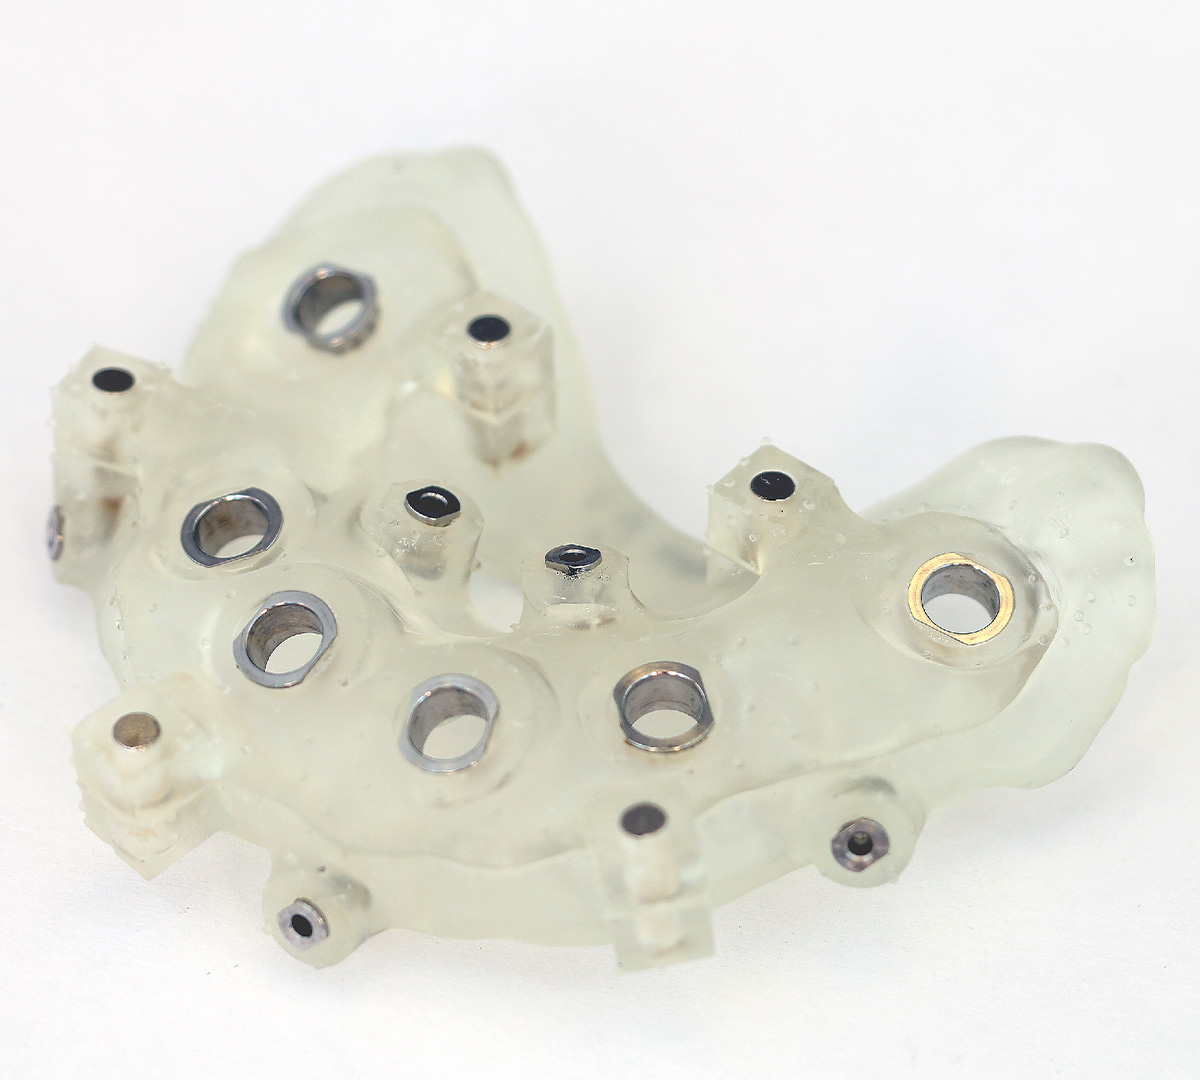

Pour garantir un positionnement optimal des implants et une stabilité à long terme, la chirurgie guidée joue un rôle essentiel. Cette technique repose sur un plan de traitement numérique détaillé, élaboré à partir d’un scanner 3D et d’une modélisation informatique.

Une fois le positionnement des implants déterminé avec précision, un guide chirurgical est imprimé en 3D pour assurer une insertion idéale des implants. Cela permet de réduire les risques, d’améliorer le confort post-opératoire et d’optimiser la durée de cicatrisation.